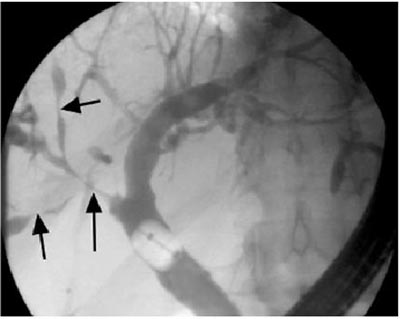

ERCP显示:多发性内胆管狭窄